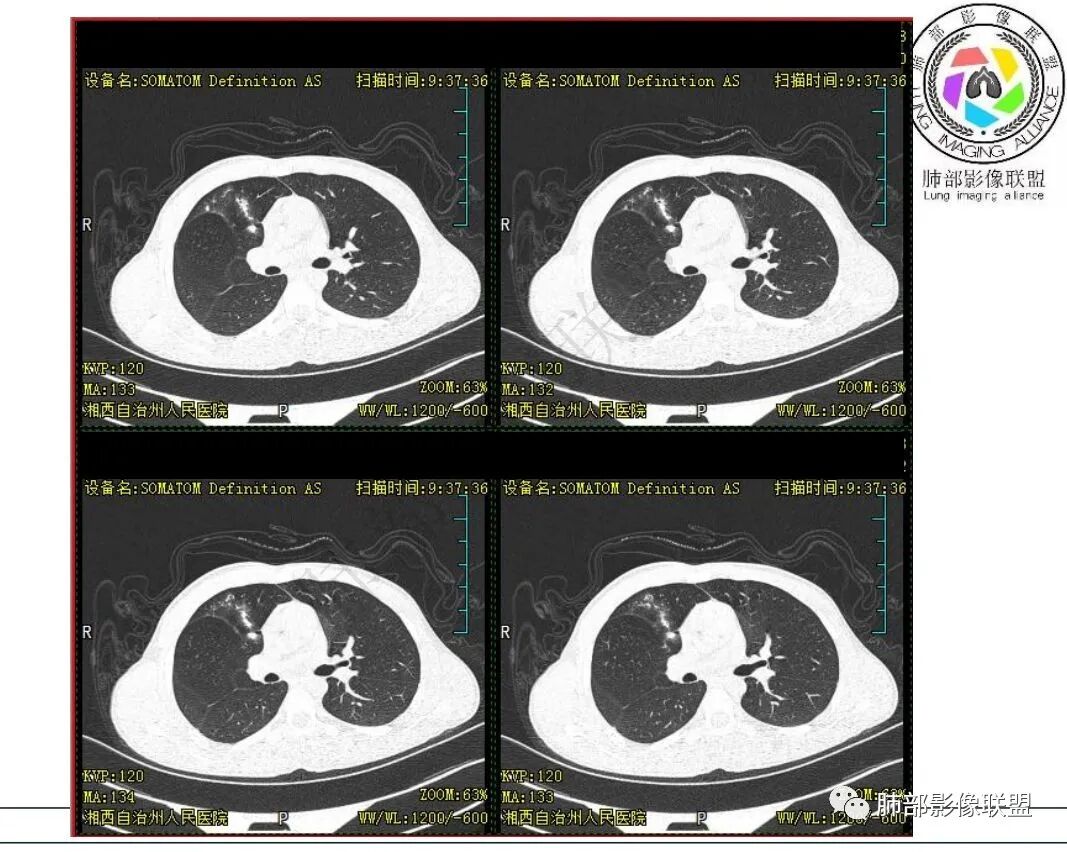

影像:右肺上叶多发实变影结节影,边界模糊,边缘收缩,伴多发空洞,洞壁光滑,部分支气管壁增厚。

3.首次CT提示:右肺上叶多发结节影及实变影,簇状分布,周围散在磨玻璃影,结节内多类圆形空洞,内壁光整,有一定张力,偶见液平。部分支气管壁增厚。

考虑良性感染性病变可能。

5.抛开分布不谈 其他的,临床中毒症状不明显、非易感人群,肺结节、实变、晕征、空洞等等都可以符合隐球感染。